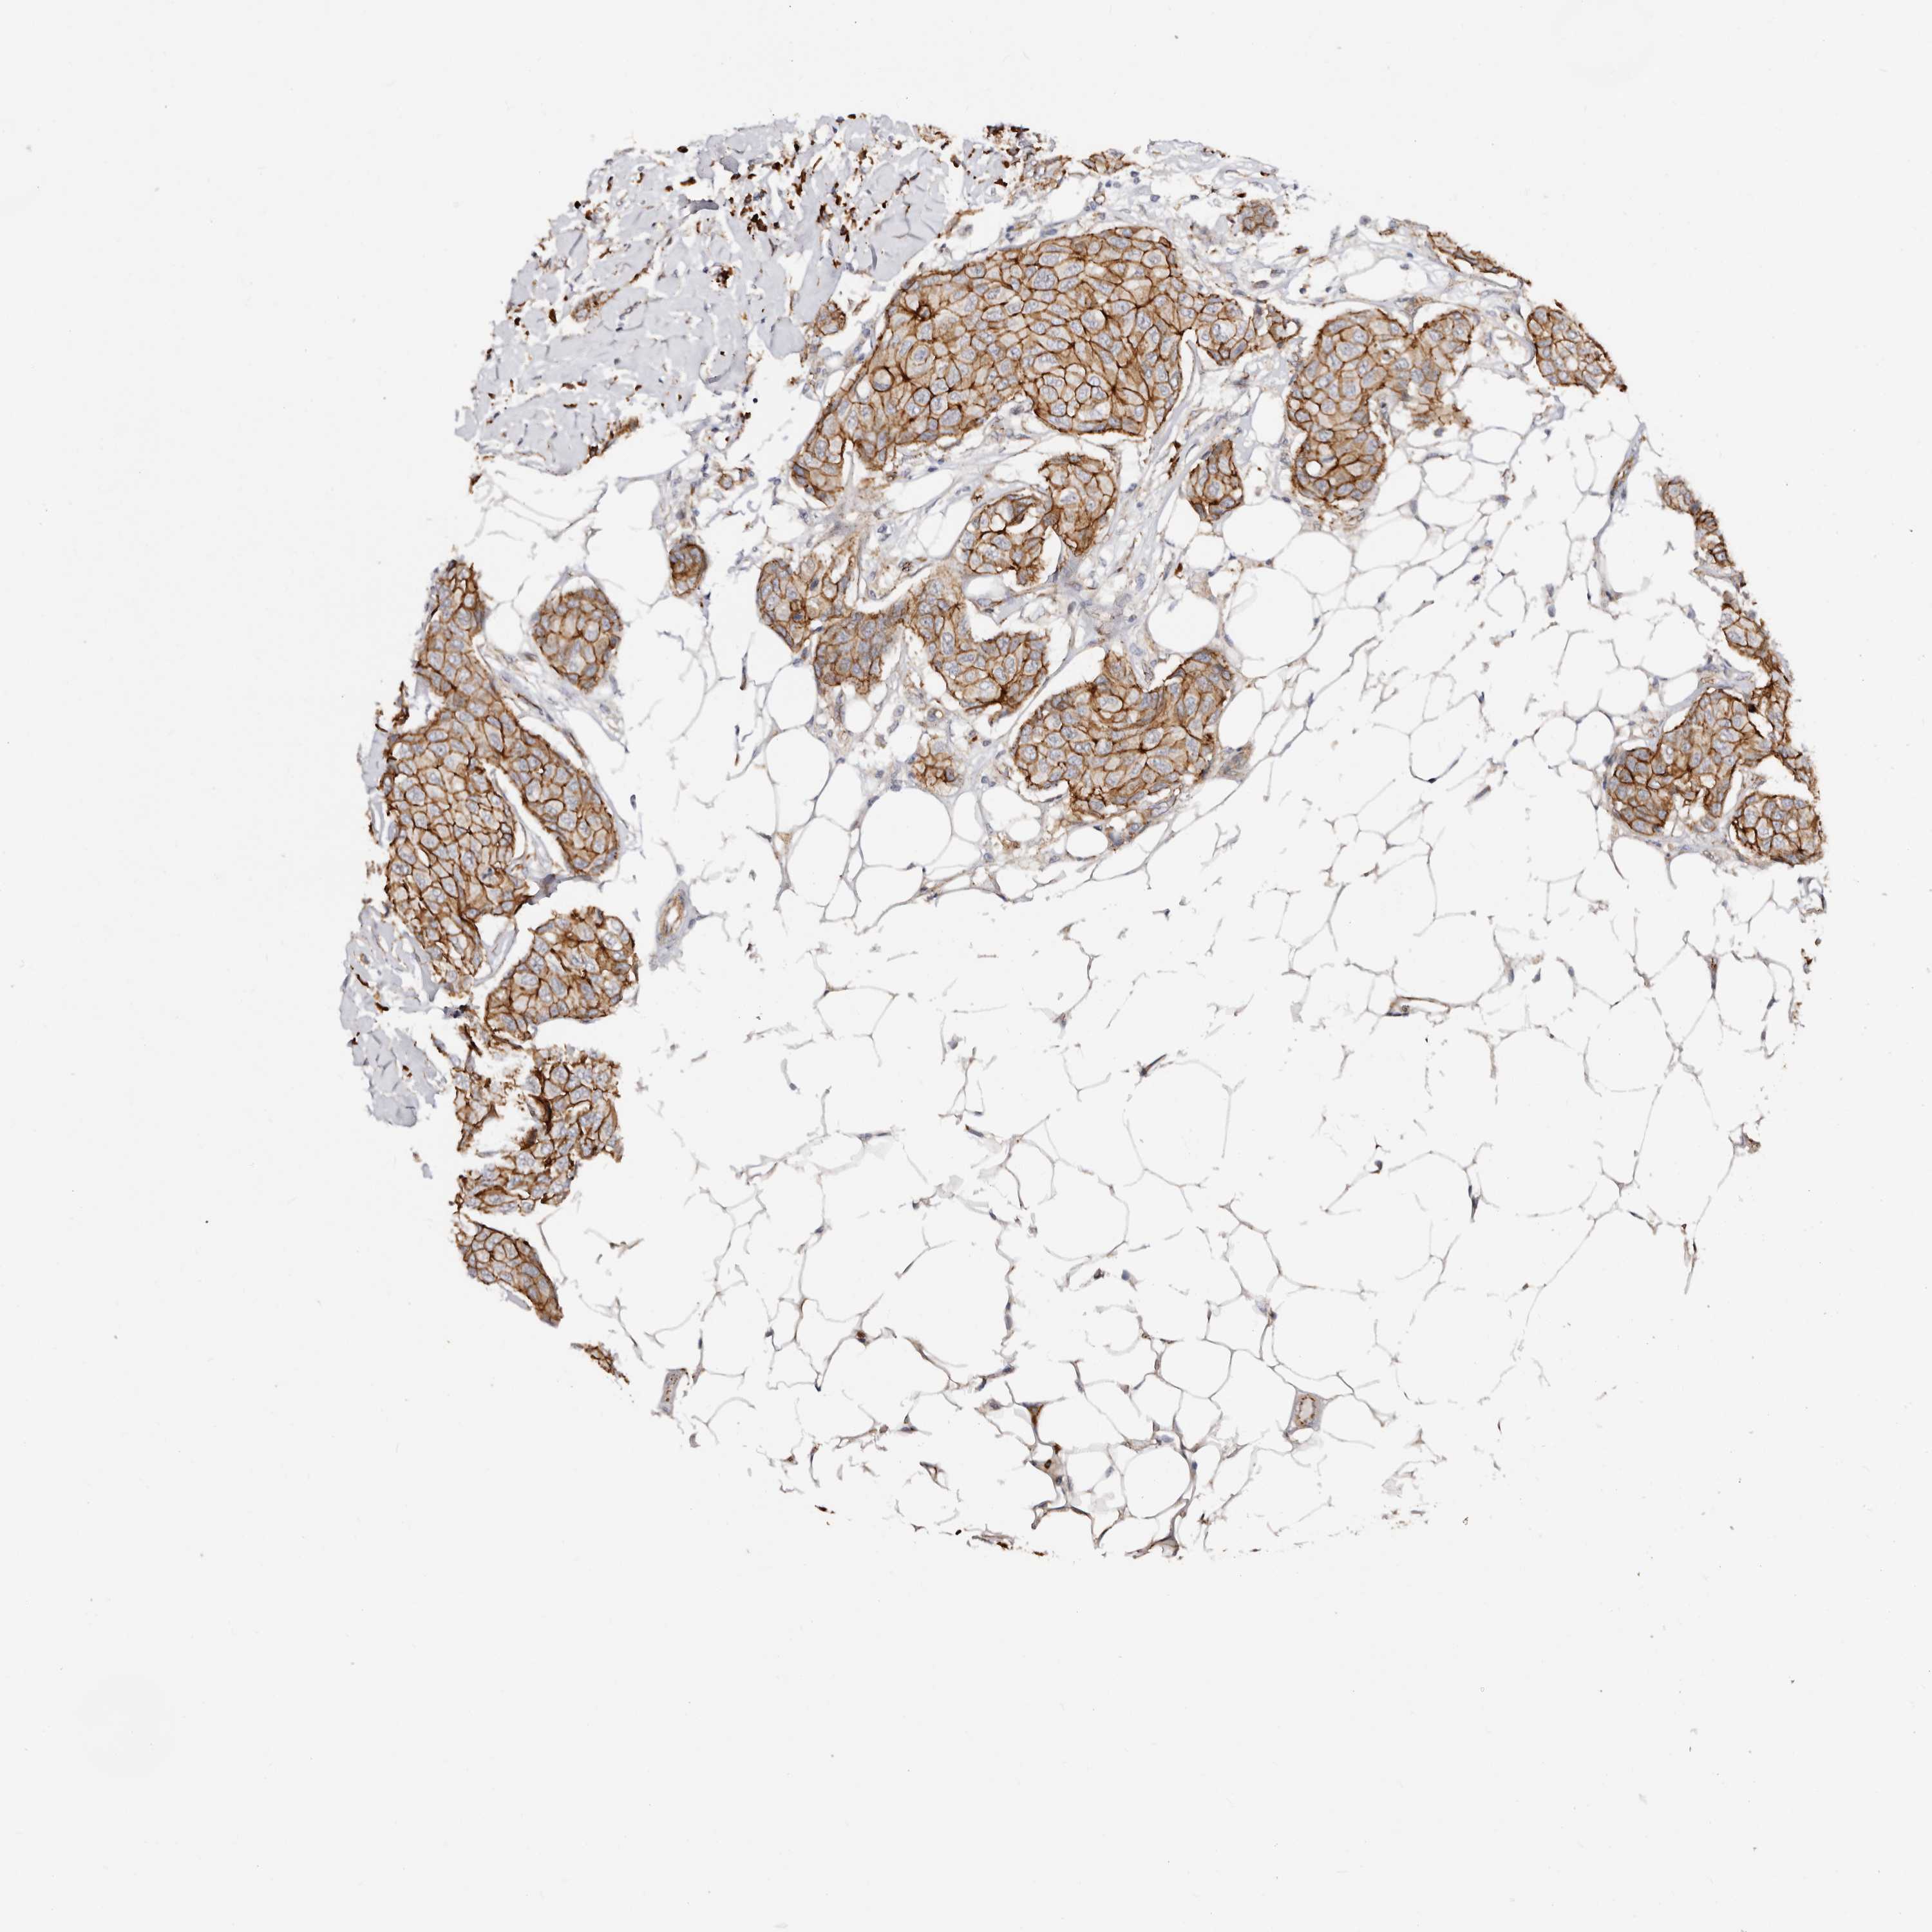

CANCER BREAST CANCER Show tissue menu

BRCA TCGA BRCA VALIDATION PROTEIN EXPRESSION